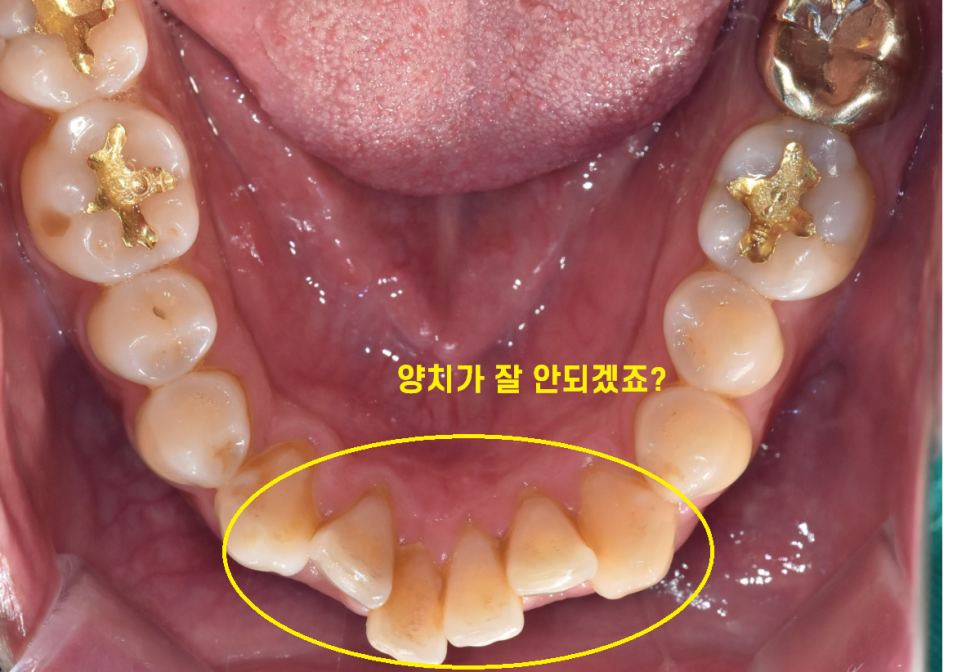

오늘의 주인공 환자분도 40대 치아교정을 문의주셨습니다.

한눈에 보기에도 치아가 삐뚤빼뚤하죠~?

치열이 고르지 않아 충치나 잇몸 질환의 위험이 높아진다.

x-ray, 구강 상태, 교합 확인

다양한 검사를 시행